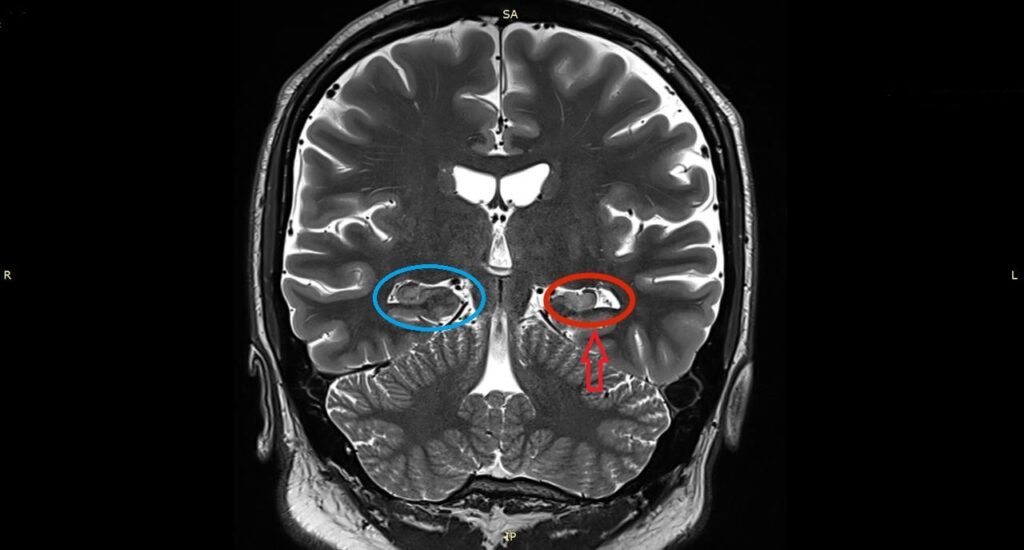

1️⃣ MRI(非常に重要)

• 海馬の萎縮

• T2/FLAIRでの高信号

→ 海馬硬化の典型所見